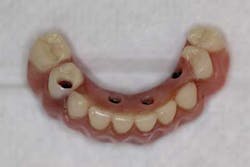

Dentures and partial dentures are treatment options that are an acceptable way to replace function and missing teeth. Unfortunately, many practitioners find the creation of said prostheses frustrating and difficult. Not only can the fabrication be challenging, but, statistically, these populations of patients have the highest percentage of dental complaints. Why? Because the loss of the problematic natural teeth is often considered a way to eliminate dental woes. Instead, a removable prosthesis is actually an introduction into a new realm of challenges. Regardless of these concerns, when treatment planned and fabricated correctly, the outcome for partials and dentures can be predictable.

5. For large spans or for full edentulism, make interim dentures/partials. By allowing the tissue and bone to heal properly, the stage is set for a better-fitting definitive prosthesis. It also gives patients an “extra set” should they lose or break their final denture/partial down the road.

The use of adhesives and inherent hassle of dentures and partials will often give rise to the incentive to look into more permanent options. Again (assuming medical history is not an issue), review implant alternatives and how patients can improve the status quo — bridges, All-On-4, implant-supported dentures, fixed hybrid prostheses, etc.